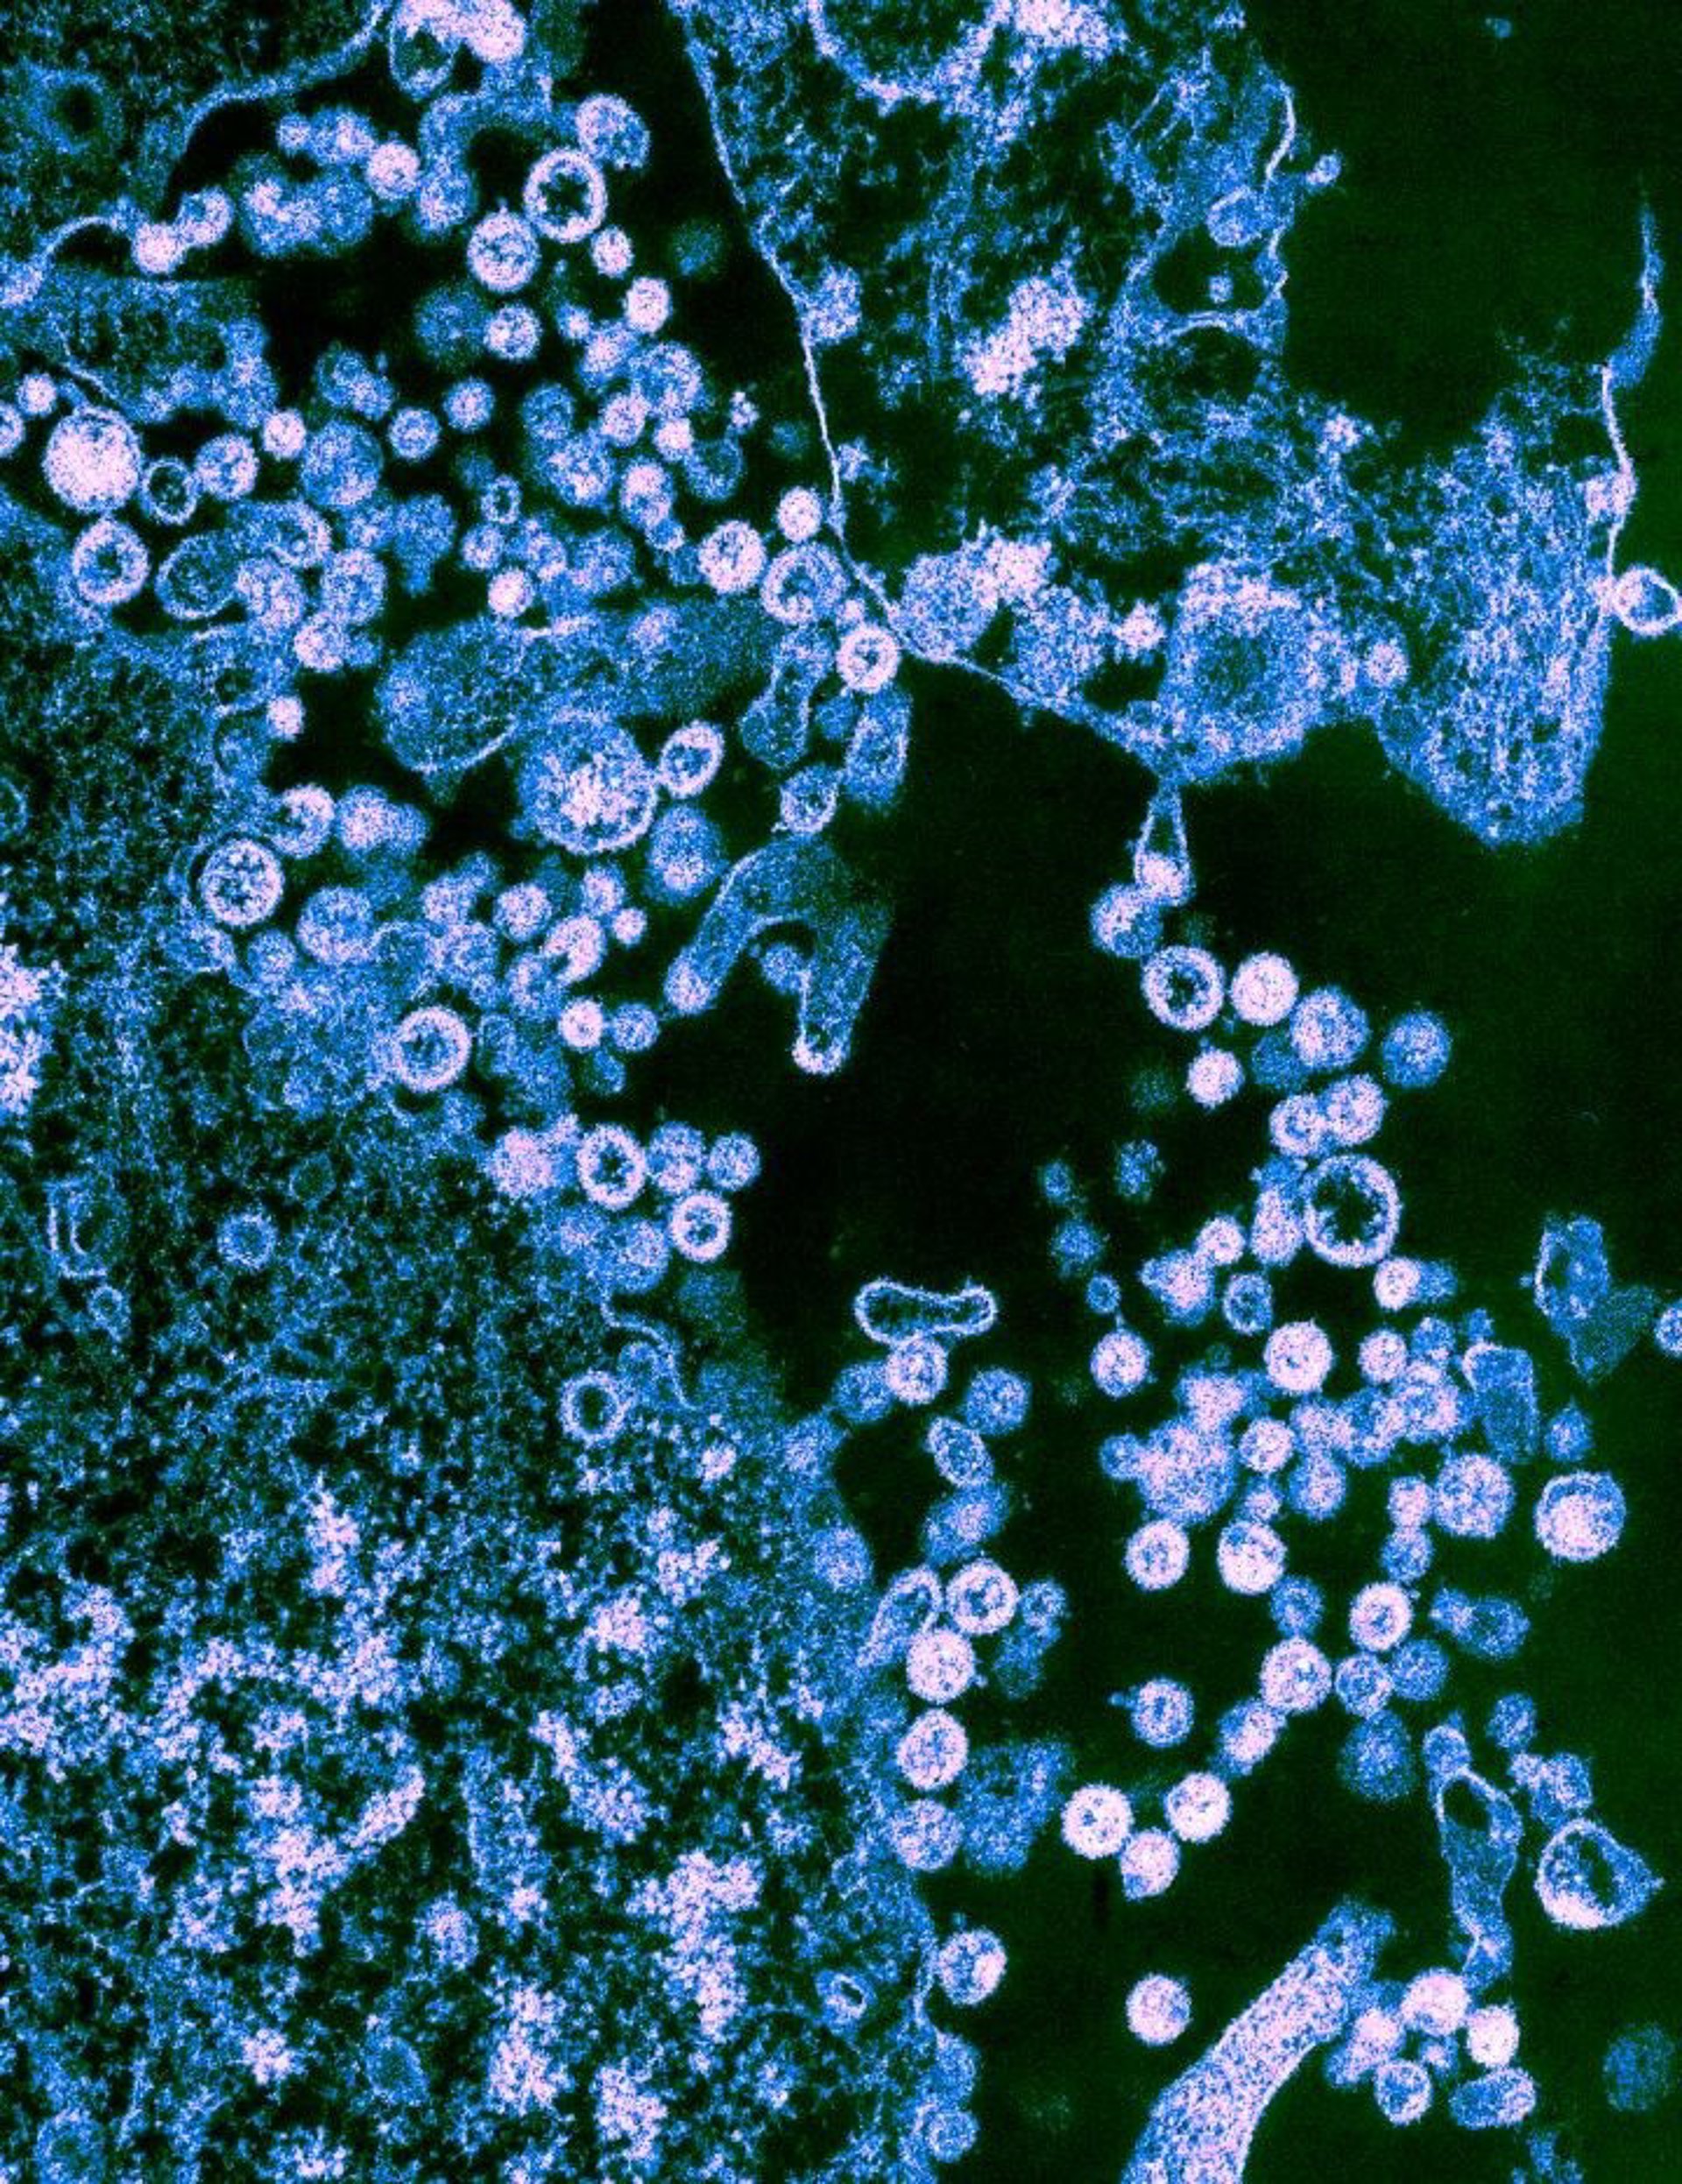

Las partículas de la cepa Josiah del virus Lassa (redondo) se muestran en gemación de las células.

Las partículas de la cepa Josiah del virus Lassa (redondo) se muestran en gemación de las células. - UNIVERSIDAD DE TEXAS